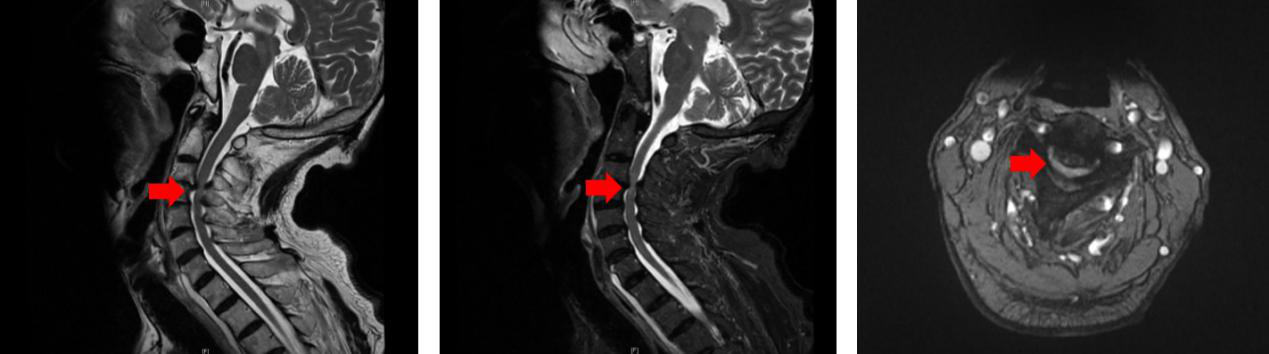

高颈段前路手术,暴露困难,手术团队凭借丰富经验,在颈动脉、气管及食管等重要结构的缝隙中,安全暴露C3-4椎体,显微镜下充分减压,使硬膜囊重新恢复搏动,保证脊髓彻底解压,最后使用钉板复位固定颈椎,手术出血仅50毫升。为了确保高龄病人术后安全平稳,术后金爷爷转入ICU病房继续治疗。ICU秦君平医师精心管理,病人顺利脱机拔管,第二天上午即转回普通病房由家人陪护。

图3 术后CT检查,颈椎复位,脊髓受压解除

在神经外科10A病区护理人员、康复科和中医科的通力配合下,金爷爷术后病情迅速好转,神经功能改善明显,可以独立下地活动,肩部疼痛较轻明显减轻,双手力量也有大幅进步,术后7天顺利出院。“感谢清华长庚医院,感谢神经外科,谢谢你们让我重获新生!”金爷爷激动地说。